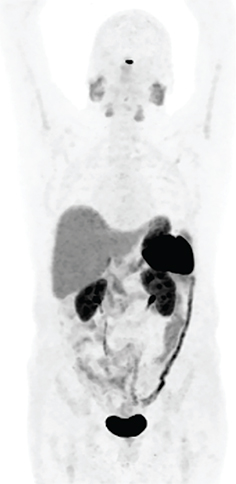

The radiopharmaceutical 111In-octreotide is a single-photon somatostatin analogue. There are many tumor types that express somatostatin receptors including adrenal medullary tumors, gastroenteropancreatic (GEP) NET, Merkel cell carcinoma, pituitary adenomas, medullary thyroid carcinoma, and small cell lung cancer. 111In-octreotide is currently falling out of favor for imaging due to its lower sensitivity compared to positron emission tomography (PET) somatostatin analog agents. However, it is important to know of this agent in the event that imaging with PET agents is not possible in a given location. It can assist in the detection and localization of the disease, staging, and follow-up of patients with somatostatin receptor-rich disease processes (2). Figure 1 shows the normal biodistribution of 111In-octreotide.

Figure 1. Normal distribution of 111In-octreotide scan. Note the prominent splenic and kidney activity, excretion in the urinary bladder and less prominent uptake in the liver and variable bowel activity.